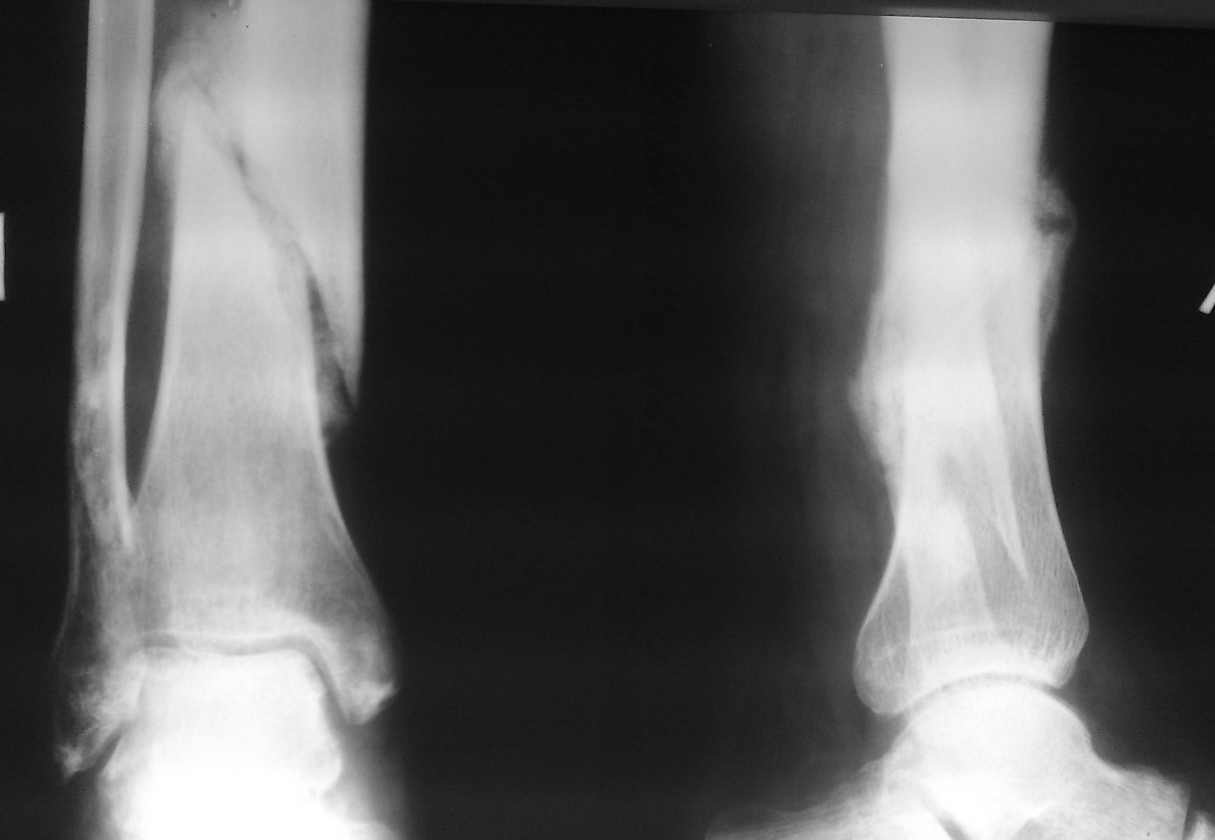

пример функционального лечения по Сармиенто похожего перелома.

Рентгенограммы в 1 мес, 3,5 мес, фото  и видео 3,5 мес.

Имя     : 1 мес бок.jpg

Тип     : image/jpeg

Размер  : 25142 байтов

Описание: отсутствует

Url     : http://weborto.net:8080/pipermail/ortho/attachments/20131127/74c4cd2f/attachment-0004.jpg

Вложение не в текстовом формате было извлечено…

Имя     : 1 мес.jpg

Размер  : 21677 байтов

Url     : http://weborto.net:8080/pipermail/ortho/attachments/20131127/74c4cd2f/attachment-0005.jpg

----------- следущая часть -----------

Имя     : 3,5 мес.jpg

Размер  : 41971 байтов

Url     : http://weborto.net:8080/pipermail/ortho/attachments/20131127/74c4cd2f/attachment-0006.jpg